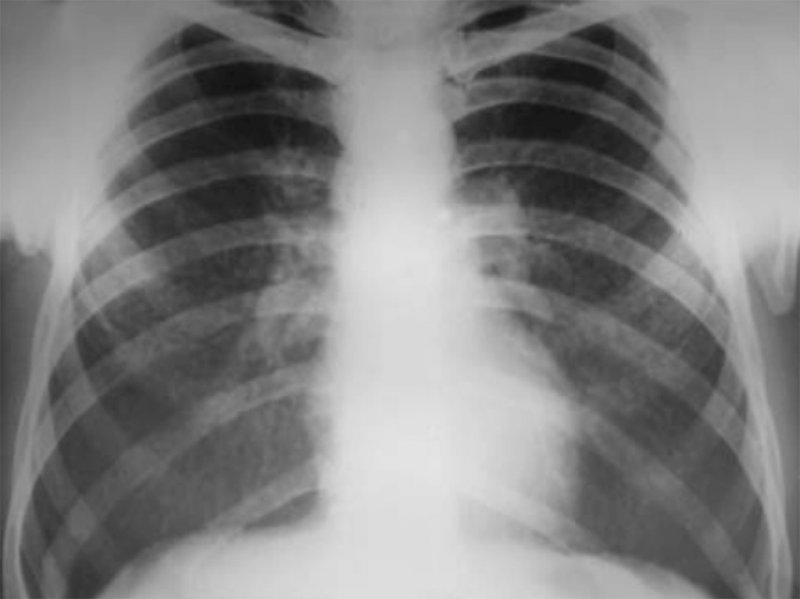

II стадия – в легких визуализируются множественные очаговые тени, размером от 5 до 10 мм – так называемая картина «снежной бури». Может определяться обызвествление узелков. Также отмечается выраженная деформация и усиление легочного рисунка с образованием ретикулярных теней (отметим, что на этом фоне сосудистый рисунок определяется плохо) (рисунок 1).

Рисунок 1. Силикоз (II стадия). В легких определяются множественные очаги обызвествления – картина «снежной бури»